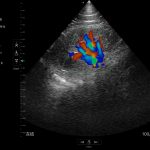

Modos de escaneo: B, B/M, Color, PW

Mediciones: Longitud, área, velocidad, FC, S/D, LVIDd, LVIDs, SV, EF

Exámenes básicos y control de flujo cardíaco o vascular en entornos clínicos y extrahospitalarios.